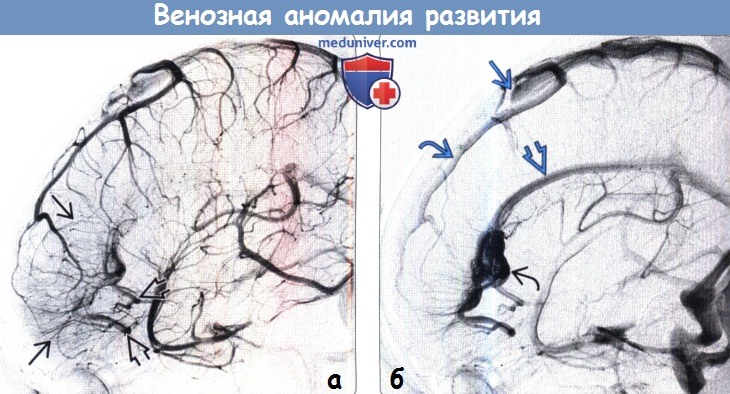

Мр картина венозной ангиомы левой гемисферы мозжечка - 96 фото